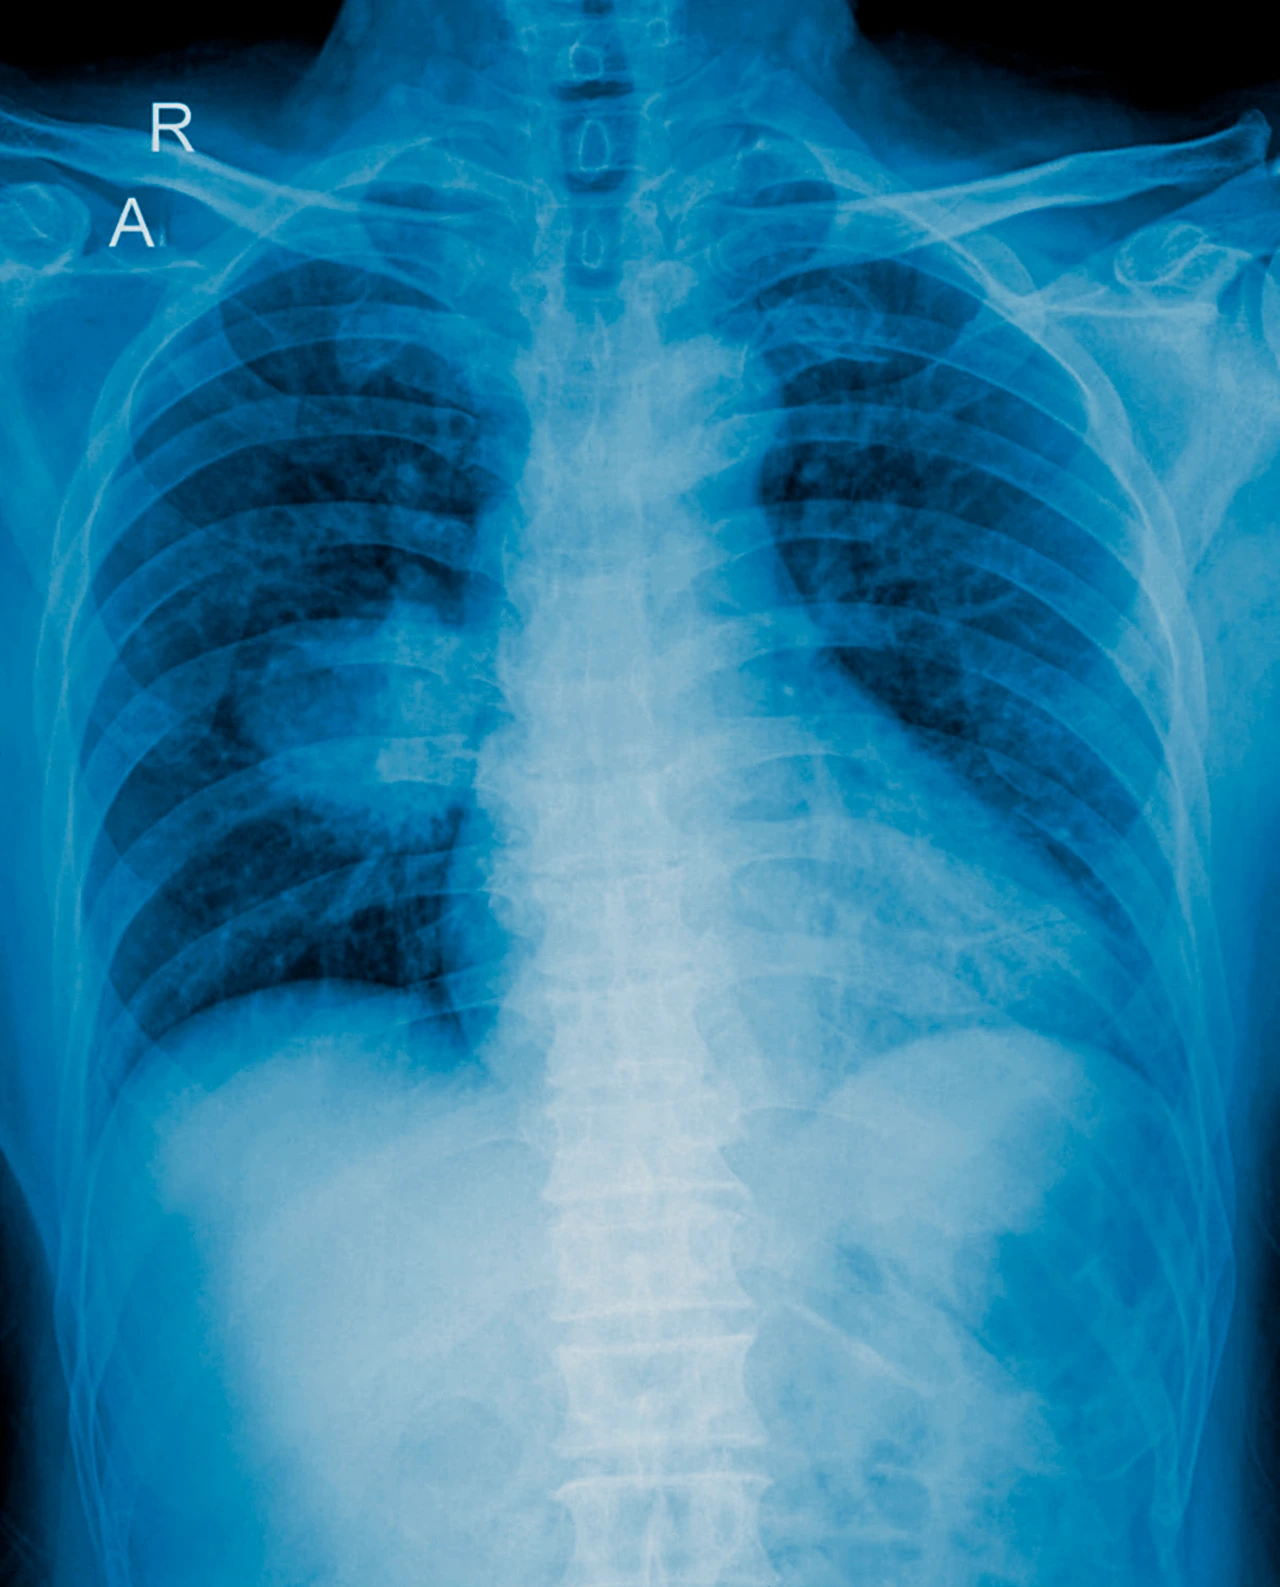

Si presentas cualquiera de los síntomas de cáncer de pulmón mencionados, especialmente si perteneces a un grupo de riesgo, no debes esperar. La consulta con un neumólogo u oncólogo es vital para realizar desde una radiografía hasta una biopsia si fuera necesario. El miedo al diagnóstico no debe frenar la búsqueda de ayuda, ya que hoy existen más opciones, en el cáncer de pulmón, de tratamiento que nunca, incluyendo inmunoterapia y terapias dirigidas.